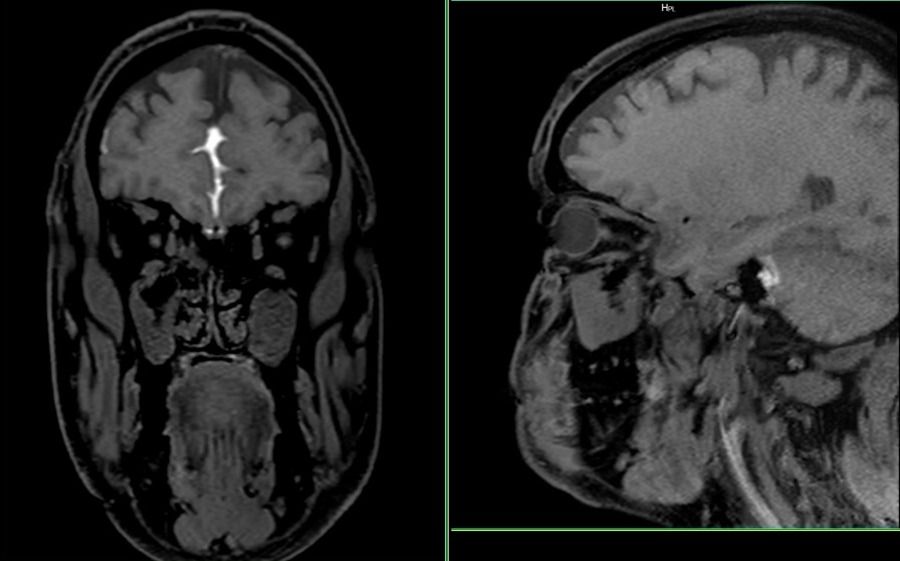

A 48-year-old male presented with a clinical suspicion of cerebrospinal fluid (CSF) rhinorrhea, characterized by persistent right-sided nasal discharge.

The study utilized a comprehensive Digital MRI Cisternography protocol on an advanced high-field system.

- Pre-contrast Sequences: Axial DWI, T2 STIR, Fat-saturated T1 (coronal and sagittal), T2 FSE coronal, and high-resolution T2 SPACE sequences for detailed anatomical assessment of the skull base.

- Post-contrast Dynamics: Performed following intrathecal gadolinium administration, utilizing T1-weighted fat-saturated images in sagittal and coronal planes at 1-hour and 2-hour intervals.

- Delayed Imaging: An additional delayed scan was performed at the 36–38 hour mark to detect intermittent or slow-flow leaks.

- CSF Leak Assessment: No continuous T1 hyperintense CSF tract was identified extending from the basal subarachnoid spaces across the cribriform plate or central skull base into the sinonasal cavity.

- Delayed Phase: No evidence of contrast extravasation was noted on scans acquired up to 38 hours post-injection.

- Sinonasal Anatomy: Moderate mucosal thickening in bilateral maxillary and ethmoid sinuses, causing obstruction of the right ostiomeatal complex. Minimal rightward nasal septal deviation and bilateral inferior turbinate hypertrophy.

- Intracranial Findings: Normal brain parenchyma with no evidence of cephalocele or focal lesions.